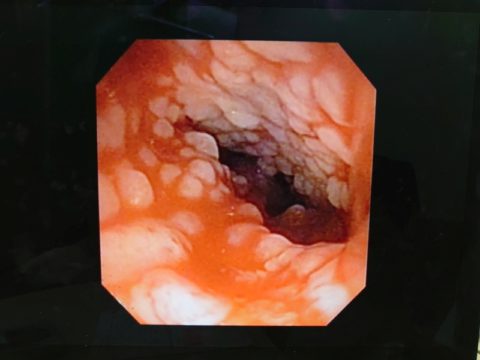

鼻咽頭内にぼこぼこしたものがへばりついてる..

確かに先日見せてもらったワンちゃんの狭窄とは異なり、空洞は広いようだけど何かがへばりついてる..

先生が言っていた「ぼこぼこしたもの」は、この白いぼこぼこのことだった

鼻咽頭内は膿とか血液とか鼻汁とかはなく、ただぼこぼこしたものが覆い尽くしている..

先生の所見では今のところこれが炎症によるものなのか、リンパ腫なのかは判断できないとのこと..

この組織を採ったので、これを病理検査と遺伝子検査に出して何なのかを調べるということになった